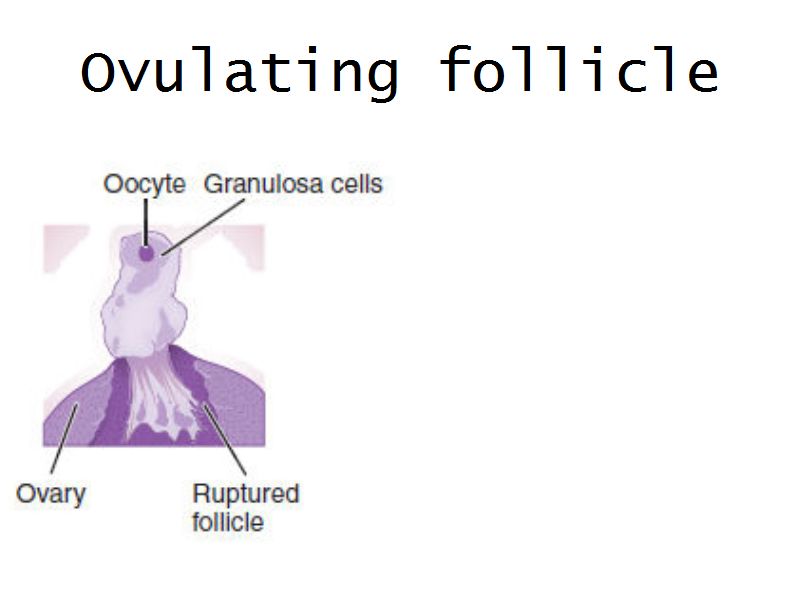

Follicular maturation

- Primordial follicle

- Growing follicle

- Primary follicle

- Secondary follicle

- Mature follicle (Graafian)

Components of a follicle

- Theca

- externa

- interna

- basal lamina

- Granulosa cells

- Antrum

- Cumulus oophorus >> Corona radiata

- Oocyte